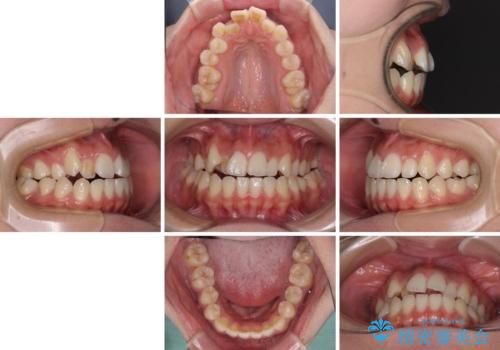

- 前歯の開咬と、上顎前歯の八重歯やデコボコを気にして来院された患者様です。

上顎歯列が狭窄していたため、急速拡大装置により上顎骨を側方に拡大し、その後ワイヤー装置にて矯正治療を行うこととしました。